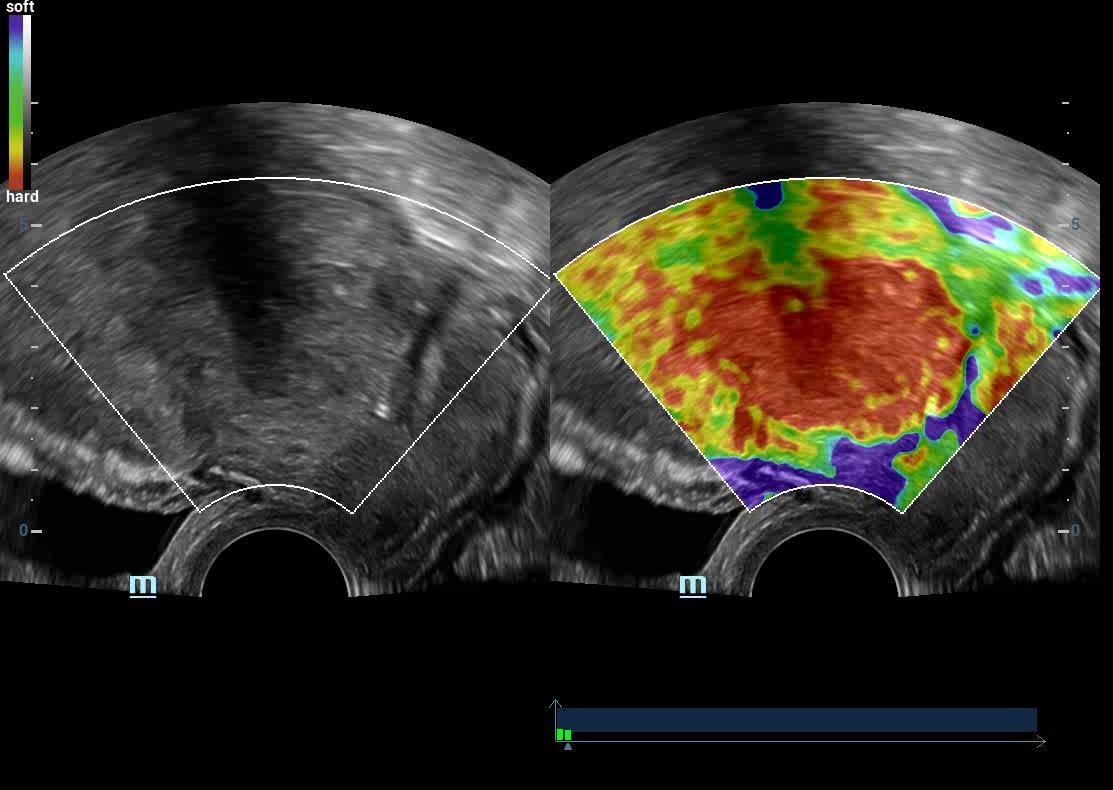

• High End SHEAR WAVE ELASTOGRAPHY For LIVER FIBROSIS/THYROID MALIGNANCY/BREAST CANCER

Liver Elastography